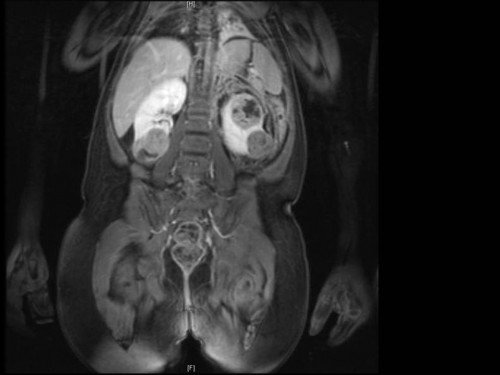

3. 3 ½ jähriges Mädchen mit posttraumatischen Bauchschmerzen

3 ½ Jahre altes Mädchen. Anamnese: Starke Bauchschmerzen nach einem Sturz vor 3 Tagen.